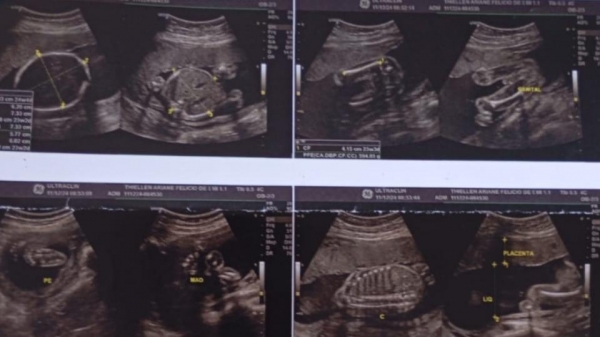

Quando os resultados chegaram, o diagnóstico era de gravidez. No documento havia detalhes de uma gestação de 23 semanas e dois dias, como até o peso do bebê. As imagens mostram o feto e há o nome da verdadeira paciente. O nome do homem também aparece gravado no laudo.